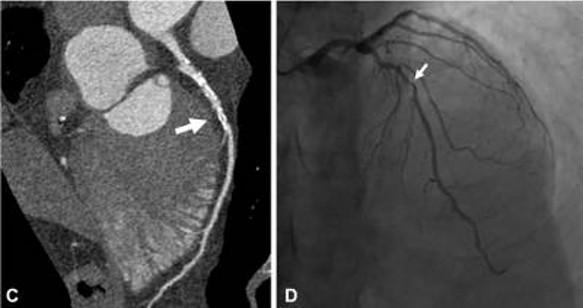

Diagnosis of CAD includes invasive coronary angiography (right), or computerized tomography coronary angiogram (left).

Picture showing diagnosis of Coronary Artery Disease via computerized tomography coronary angiogram on the left and invasive coronary angiography on the right.

Images from Latina et al. Radiology: Cardiothoracic Imaging 2021; 3(4):e210053 doi: 10.1148/ryct.2021210053.